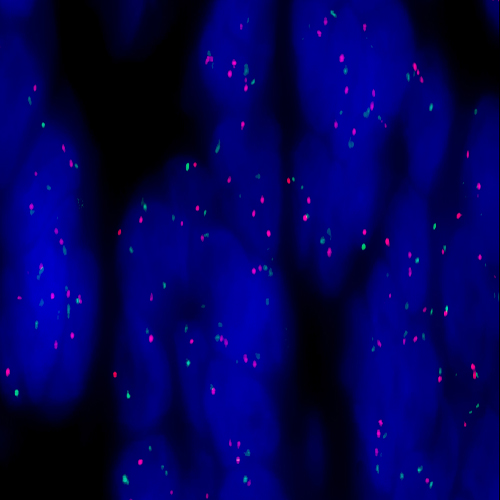

Adenocarcinoma of the lung stained using Kreatech MET (7q31) / SE7(D7Z1)

XL probe for BOND (KBI-XL003).

MET (7q31) / SE7 (D7Z1) - XL for BOND FISH probe detects genomic amplifications involving the MET gene. MET (7q31) - XL is optimized to detect copy numbers of the MET gene region at 7q31. SE7 (D7Z1) - XL is optimized to detect copy numbers of the chromosome 7 centromere.

When combined, both probes are used to detect amplification of the MET gene at 7q31, using the centromeric probe as a control.